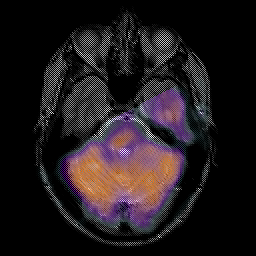

Glioma overlay -- Slice #8

[Home][Help][Clinical] Slice 8